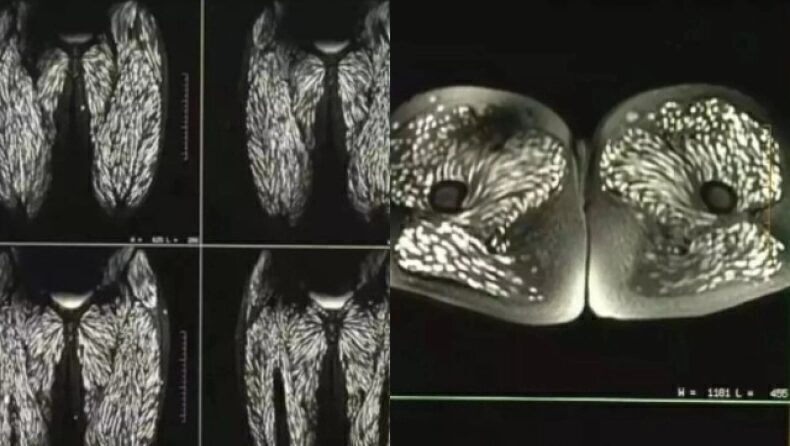

Ο γιατρός των επειγόντων περιστατικών, Δρ. Sam Ghali, μοιράστηκε μια τρομακτική αξονική τομογραφία των μυών των ποδιών ενός ασθενούς με παρασιτική λοίμωξη την Κυριακή στο X.

Στη συνέχεια, οι προνύμφες εκκολάπτονται και «διεισδύουν στο εντερικό τοίχωμα και εισβάλλουν στην κυκλοφορία του αίματος», εξαπλώνοντας ελεύθερα σε όλο το ανθρώπινο σώμα και σχηματίζοντας μια σκληρή ασβεστοποιημένη κύστη στον μυ ή στον εγκέφαλο που μπορεί να αισθάνεται σαν εξογκώματα κάτω από το δέρμα.

Θα εμφανιστούν τόσο μικρές λευκές κηλίδες όσο δείχνει η αξονική τομογραφία που μοιράστηκε ο γιατρός και αναφέρονται ως «αποτιτανώσεις κόκκων ρυζιού».